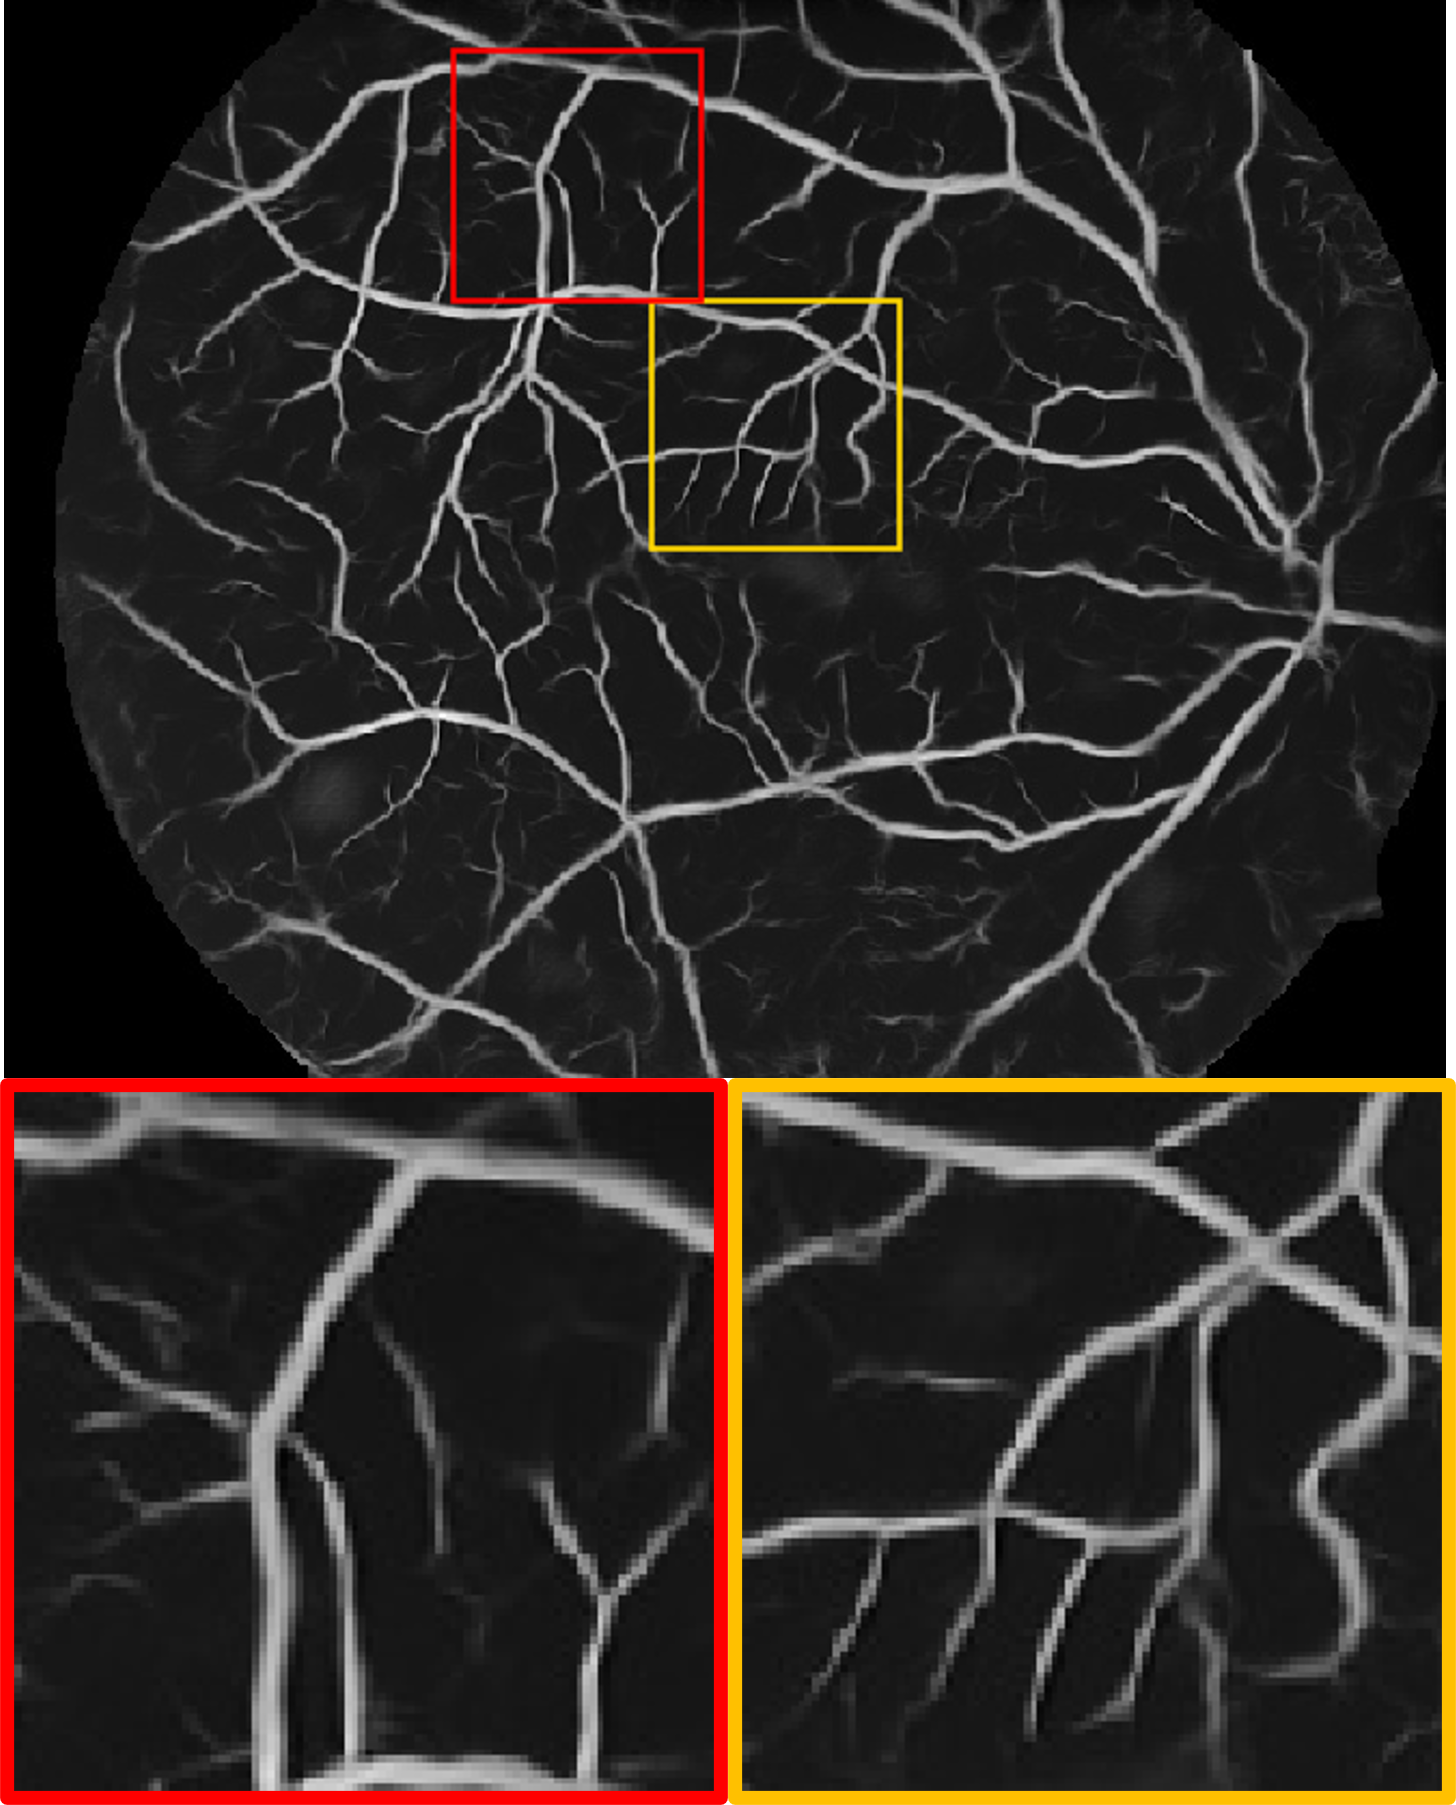

Datasets. We use four publicly available fundus datasets as shown in Fig. 1(b). The DRIVE dataset [15] consists of 20 labelled images of size . The HRF dataset [16] contains 45 labelled images of size . The STARE dataset [17] includes 20 labelled images of size . The ARIA dataset [18] includes 138 labelled images of size . DRIVE and HRF are set as source domain, whereas STARE and ARIA are used for testing.

Fig. 2 shows a test example from each of the target domains. We observe that for different datasets, the manual annotations includes varying amounts of detail: the label for the STARE dataset contains many more small vessels than ARIA. In the ARIA example, the deep angiogram is able to enhance the thin vessels with very poor contrast. This is also evident by the big vessels seen at the bottom left quadrant of the image where the illumination is low. Moreover, the angiogram filters out the circular artifacts seen within the red box. In the STARE example, our model extracts most of the vasculature including the faintly visible fine vessels. These tiny vessels have relatively lower intensity in the deep angiogram, which suggests lower confidence. Compared to the manual label, the deep angiogram can also delineate the vessel diameter more precisely.